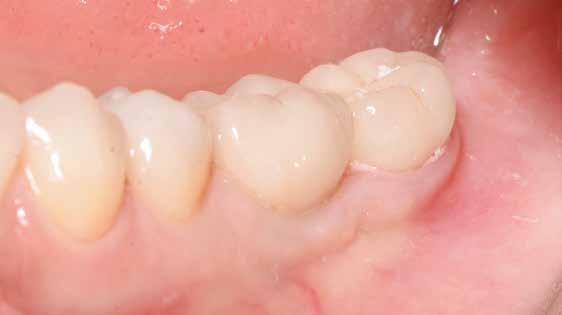

lási csavarokat (PEEK titáncsavarral) maximum 15 Ncm-rel húztuk meg (3–6. ábra). Az összes implantátum kiváló stabilitást mutatott (a mérésekhez Periotestet használtunk, a Medizintechnik Gulden jóvoltából), és teljesen osszeointegrálódott. Ezt a radiológiai vizsgálatok is megerősítették.

Digitális intraorális scan

Egy héttel a második műtét után intraorális szkennelést végeztünk Medit i500 scannerrel (Medit), a gyártó szkennelési protokollját követve (7. ábra). A gyógyulási csavarok eltávolítása után CERALOG scanbodykat (PEEK-titánötvözet csavar) helyeztünk el az implantátumokba. A fogszín meghatározását digitálisan, a Rayplicker (Borea) segítségével végeztük. A protetikai pótlás tervezéséhez poliphenilszulfon felépítményeket alkalmaztunk. Minden koronát digitálisan rendeltünk ugyanabból a fogászati laboratóriumból, és kerámiakoronákat választottunk minden esetben.

A koronák átadása

Átlagosan két héttel a szkennelés után a koronákat felhelyeztük, PEEK felépítményeket használtunk. Az összes koro-

na csavarozhatóan készült el. Mivel a négy páciens szigorúan a bioholisztikus megközelítés mellett döntött, a hat titán felépítménycsavart hat aranycsavarra (Holisticor csavarok) cseréltük ki. Ezeket az aranycsavarokat maximum 15 Ncm nyomatékkal húztuk meg. Titáncsavarok használata esetén legfeljebb 25 Ncm nyomatékot kell alkalmazni. A cég ajánlásának megfelelően az összes csavart legalább 5 perc elteltével újra meghúztuk a megfelelő nyomatékkal (15 Ncm). A csavarokat PTFE szalag védte, a fennmaradó csavarnyílásokat a cirkóniakoronával megegyező színű kompozitanyaggal fedtük. Az okklúziót ellenőriztük, és szükség esetén beállí-

tottuk (az okklúziós koncepciók alapján az implantációs pótlások nem voltak vezető fogak, és csak könnyű érintkezéseket alakítottunk ki, amelyeket artikulációs papírral ellenőriztünk). A páciensek instrukciókat kaptak a megfelelő szájhigiénére vonatkozóan, összpontosítva a fogköz kefékkel történő tisztítására. Végső kontroll röntgenfelvétel készült. A PEEK felépítmény nem radioopák, így az implantátum és a korona közötti távolság könnyen meghatározható a röntgenfelvételen: a felépítmény megfelelően illeszkedik az implantátumban, ha az implantátum válla és a korona alsó széle közötti rés 0,55 mm a röntgenfelvételen (8–11. ábra)